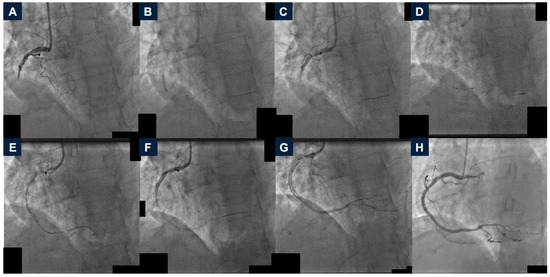

2.1. Case 1